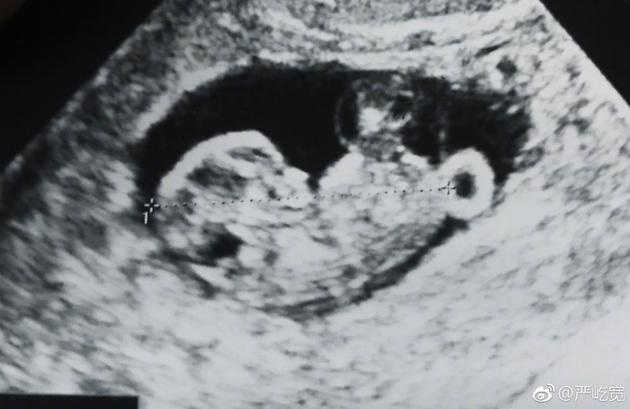

嚴屹寬曬出寶寶的B超照片

新浪娛樂訊 1月24日是嚴屹寬的生日,他在生日當天宣布了即將升級當爸的喜訊,并曬出了妻子杜若溪孕檢的照片,并發文感謝妻子,稱收到了“最好的生日禮物”。杜若溪隨后轉發為老公送上生日祝福。

24日早,嚴屹寬在微博曬出妻子孕檢的照片以及兩人的合照宣布妻子懷孕:“收到了最好的生日禮物,感謝我的肉肉”,并艾特妻子杜若溪本人的微博。隨后嚴屹寬將這條微博置頂。在三十九歲生日這天,嚴屹寬宣布妻子懷孕的消息并與網友們分享,一家人幸福滿滿,令人羨慕。